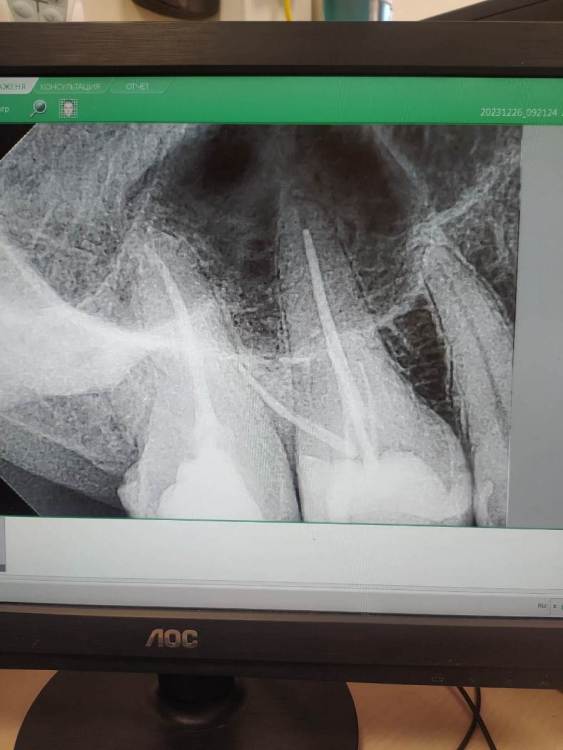

Pик Опубликовано 27 декабря, 2023 Поделиться Опубликовано 27 декабря, 2023 (изменено) Доброй ночи. Обратился в стоматологическую поликлинику. Обнаружили пульпит верхней 6 справа. Врач определил по рентгену что 6ка - 3 х канальная, до этого мне другой врач в этой стоматологии направлял на к-т и бегло посмотрев сказал что у меня периодонтит, о чем я уже сообщил лечащему. Врач удивился сказал что на рентгене этого не видит, возможно из за пазухи носа. Заложили кальций. Через 3 дня я взвыл и в выходной помчал к дежурному врачу. Сказали бывает реакция на кальций и поменяли на депульпин или похожее название. Зуб стал успокаиваться... На следующем приёме, после извлечения лекарства , стоматолог усомнился в количестве каналов и в итоге обнаружил ещё 1 канал - 4ый ! Всё по новой, заложили кальций. Через уже 2 дня произошло всё тоже самое. Опять меняем лекарство на депульпин. Тут стоматолог предположил что трещина под десной и всё таки воспаление не в каналах а между корнями.... Ждём неделю. Я параллельно иду ещё на консультацию, там делают рентген, говорят что всё в порядке воспаления не видят вообще . Зуб не болит при постукивании, при надкусывание - а только иногда дёргает, как иголочки. Говорят должно пройти. Буквально 3 дня назад запломбировали каналы. Пломбу ещё не ставили. Склоняюсь к удалению, потому что зуб все так же дёргает ... При надкусывании и постукивании не болит.! И вот на работе разговорился с коллегой, она поведала историю что у неё в одном зубе обнаружили 6 каналов. Ради интереса полез сам на к-т. Послушал видео урок как что смотреть. Обнаружил вот это. Причём такое наблюдаю только на этом зубе. Зуб,к слову очень необычной формы, какой то большой продолговатый, со скаловидным дефектом. Подскажите может и правда это тот случай когда есть ещё 2 канала, которые не заметил врач. К-т сделано до пломбировки каналов. P. S. то что надо менять клинику понимаю, но я пришёл в государственную на платной основе... Изменено 27 декабря, 2023 пользователем Pик Плохое качество снимка Ссылка на комментарий

Pик Опубликовано 28 декабря, 2023 Автор Поделиться Опубликовано 28 декабря, 2023 Добавляю снимок запломбированного зуба. Может тут что то видно Ссылка на комментарий